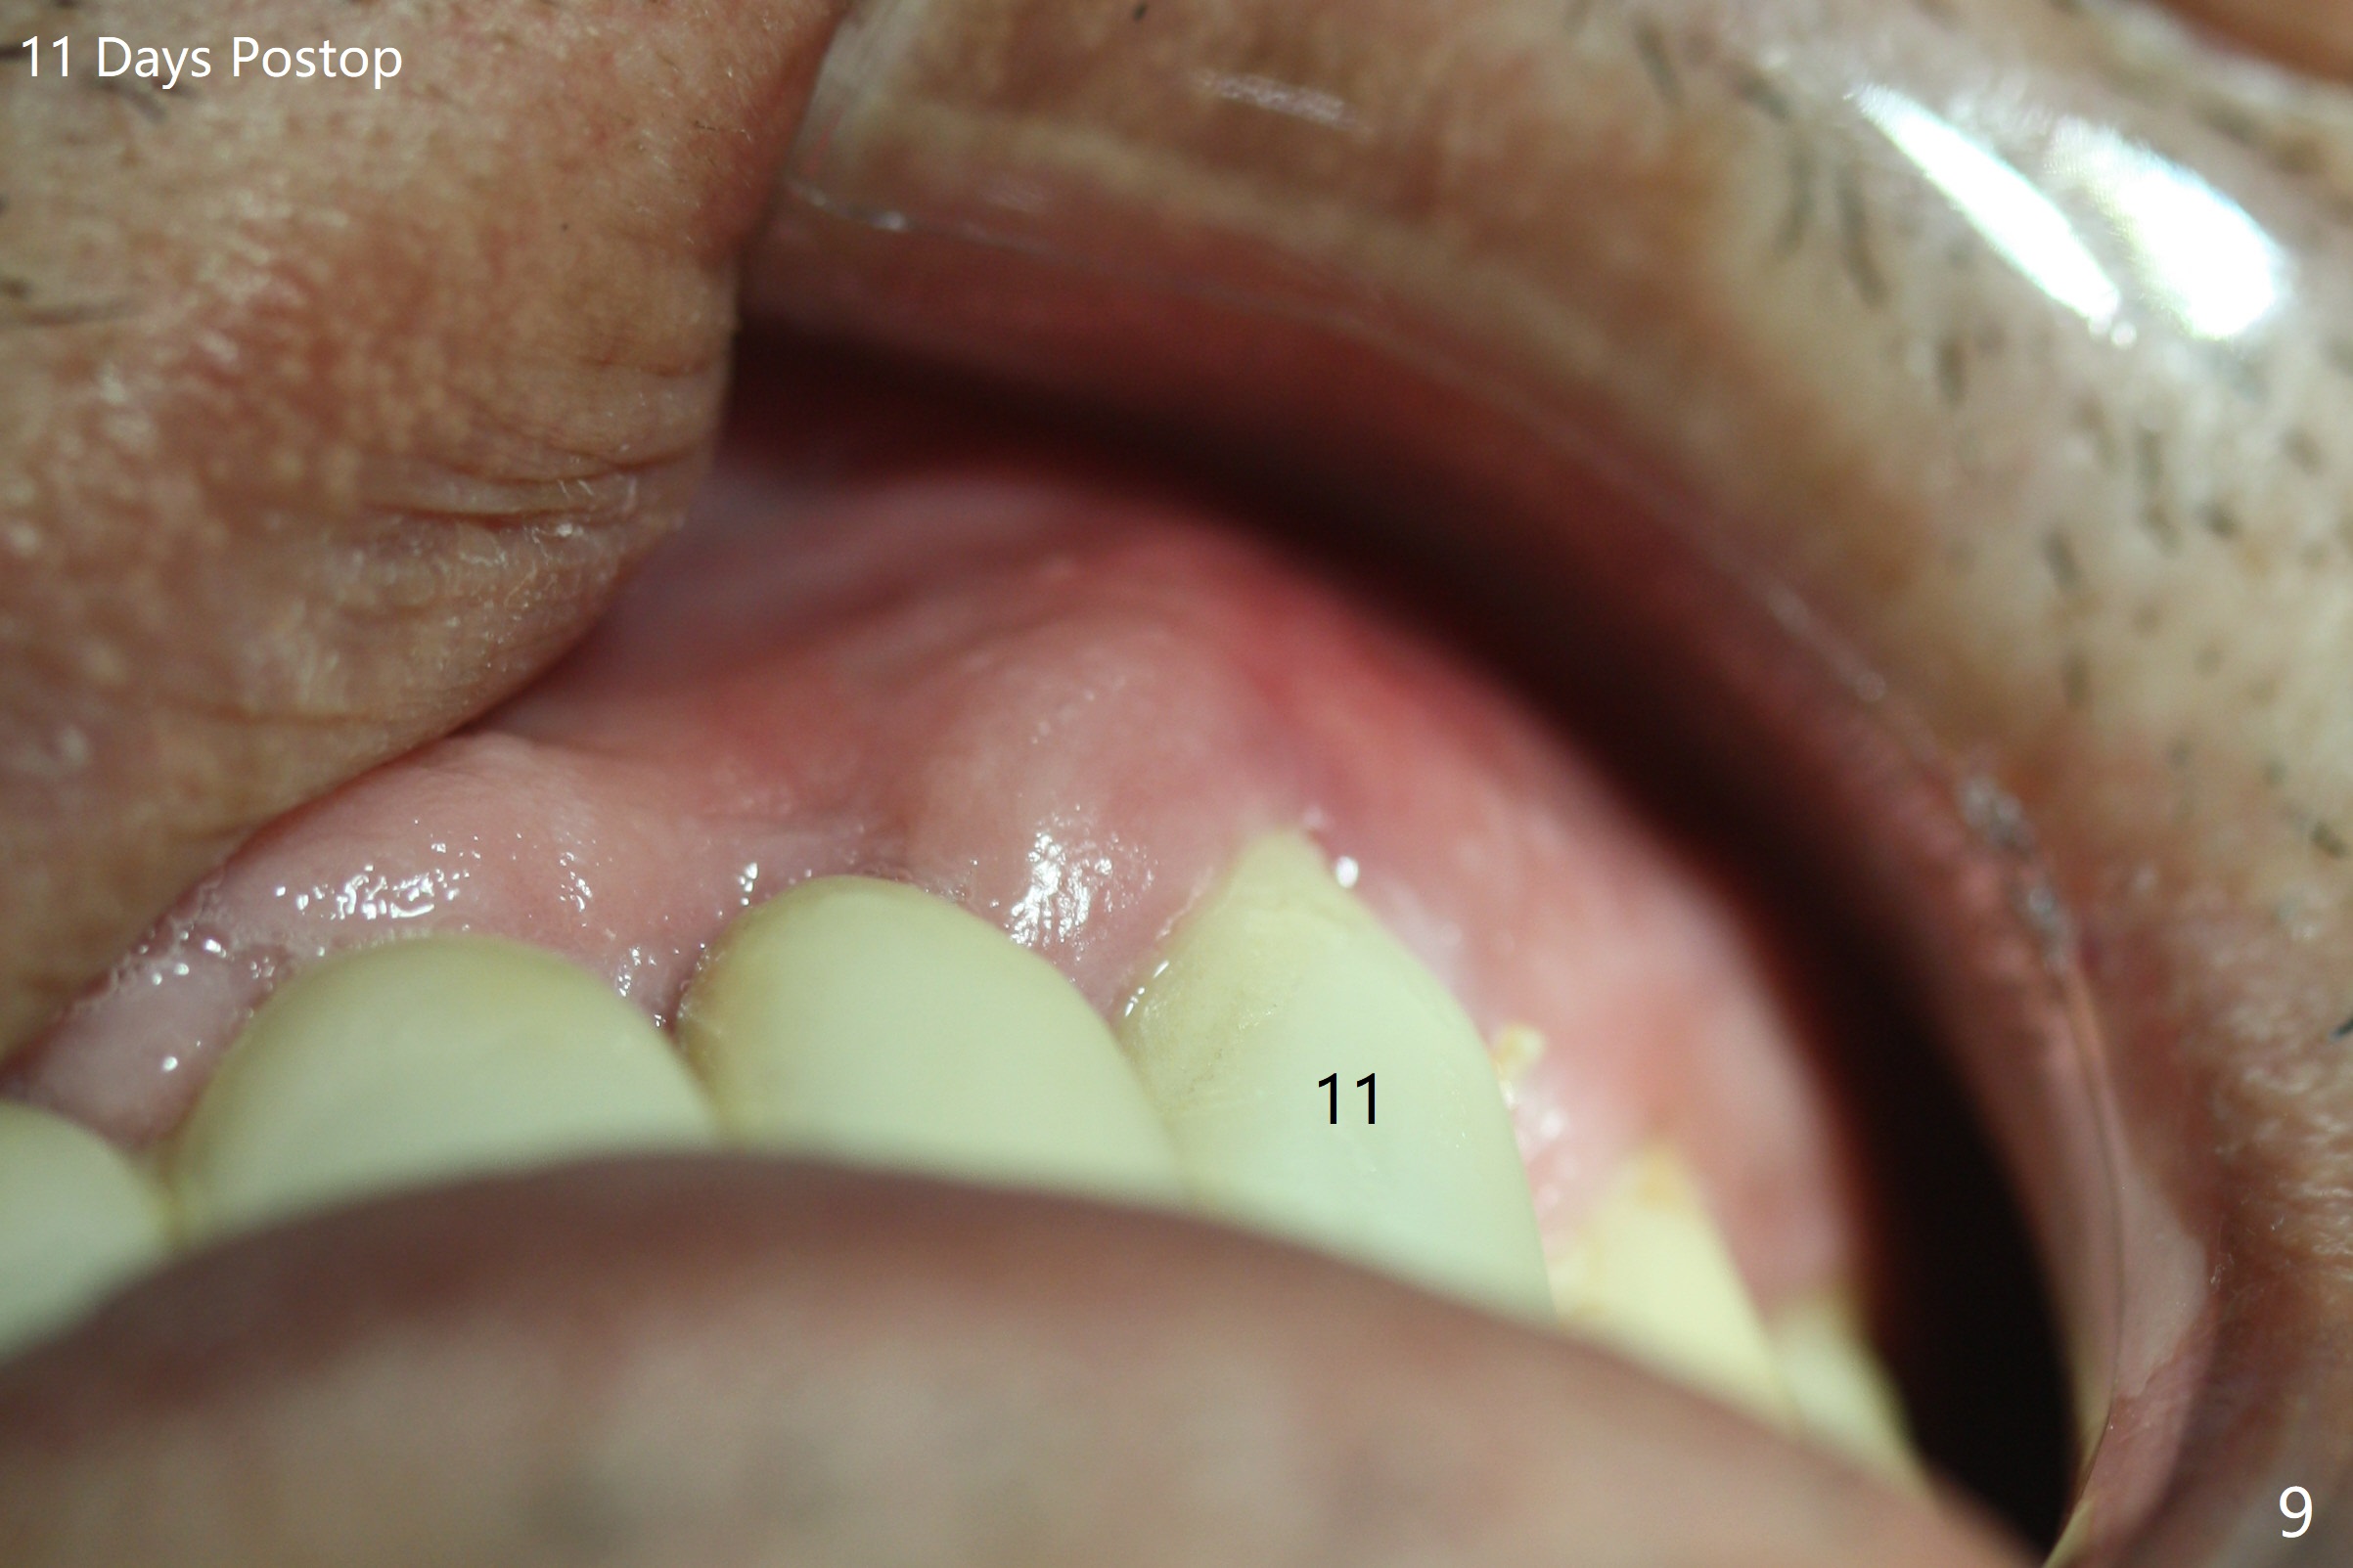

The buccal plate at #10 undergoes atrophy 9 months post immediate implant (Fig.1 *). To prevent the same post-extraction complication at #11, a technique called socket shield is going to be adopted. The buccal portion of the root (Fig.2-6 R, half-moon shaped) remains in place while a 3.5x13 mm implant is placed in the palatal portion of the socket (>50 Ncm). In fact the root is trimmed slightly subcrestal (Fig.6 C). It is assumed that there will be no or minimal bone resorption as long as the periosteum between the buccal plate and the remaining buccal root is not disturbed after tooth removal. After placement of a 4.5x15 degrees A (2mm) angled abutment and Vanilla graft (Fig.7 *), an immediate provisional is fabricated (using a central incisor crown form for #10 because of extra wide space of #11, Fig.8). There is no buccal plate atrophy at the canine 11 days postop (Fig.9). There is smooth transition from the grafted bone to the native bone 4.5 months postop (Fig.10). The buccal plate remains non-atrophic at the canine 4.5 months postop (Fig.11,12). CT taken 1 month post cementation shows that the implants at #10 and 11 are placed somewhat lingually (Fig.13,14 L (*: socket shield)). Gingival swelling is noted (Fig.15 *) with +Bleeding On Probing (^) 8 months post cementation (at the time of #21/24 impression). It appears that the socket shield (Fig.16 S) causes infection and loss of bone graft (*). The shield will be removed with an oblique accessory incision to save the papilla between #10 and 11 (Fig.17 black line). Prepare PRF for sticky bone (x1).